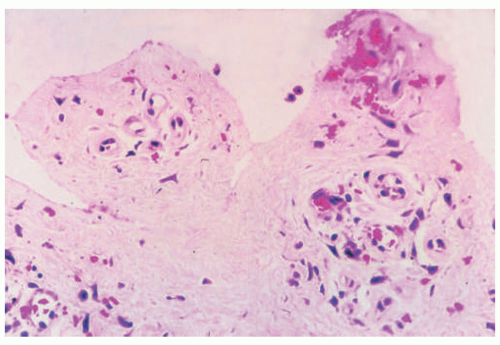

The different subtypes of porphyrias and pseudoporphyria appear histologically similar. When blister formation is present, histologic sections generally show a subepidermal blister that is free of cells or cellular debris (Figure 4-19). Lesions typically exhibit a small amount of associated chronic inflammation. The key histologic feature in the porphyrias is the presence of thick-walled, hyalinized vessels within the superficial (and sometimes deep) dermis. Periodic acid Schiff (PAS) staining highlights the material surrounding the blood vessels and may also demonstrate PAS-positive globules along the epidermal portion (roof) of the blister (sometimes referred to as “caterpillar bodies”) (Figure 4-20).22,23,24 The lesions may also show sclerosis of the dermis, and festooning (the presence of residual dermal papillae structures pushing into the blister cavity) is often a feature (Figure 4-21).22,23,24 On the basis of ultrastructural studies and antigen mapping, the level of splitting in the blisters is variable, but most often involves the lamida lucida.25 Accordingly, DIF or ICH antigen mapping studies most often demonstrate type IV collagen and laminin along the floor of the blister, and BP-1 antigen along the roof of the blister.25 DIF testing also shows the deposition of C3, IgG, and IgM around vessels in the superficial dermis (sometimes described as “doughnut-like” blood vessels, because of their thickened appearance).26 Indirect immunofluorescence (IIF) is negative in these disorders.